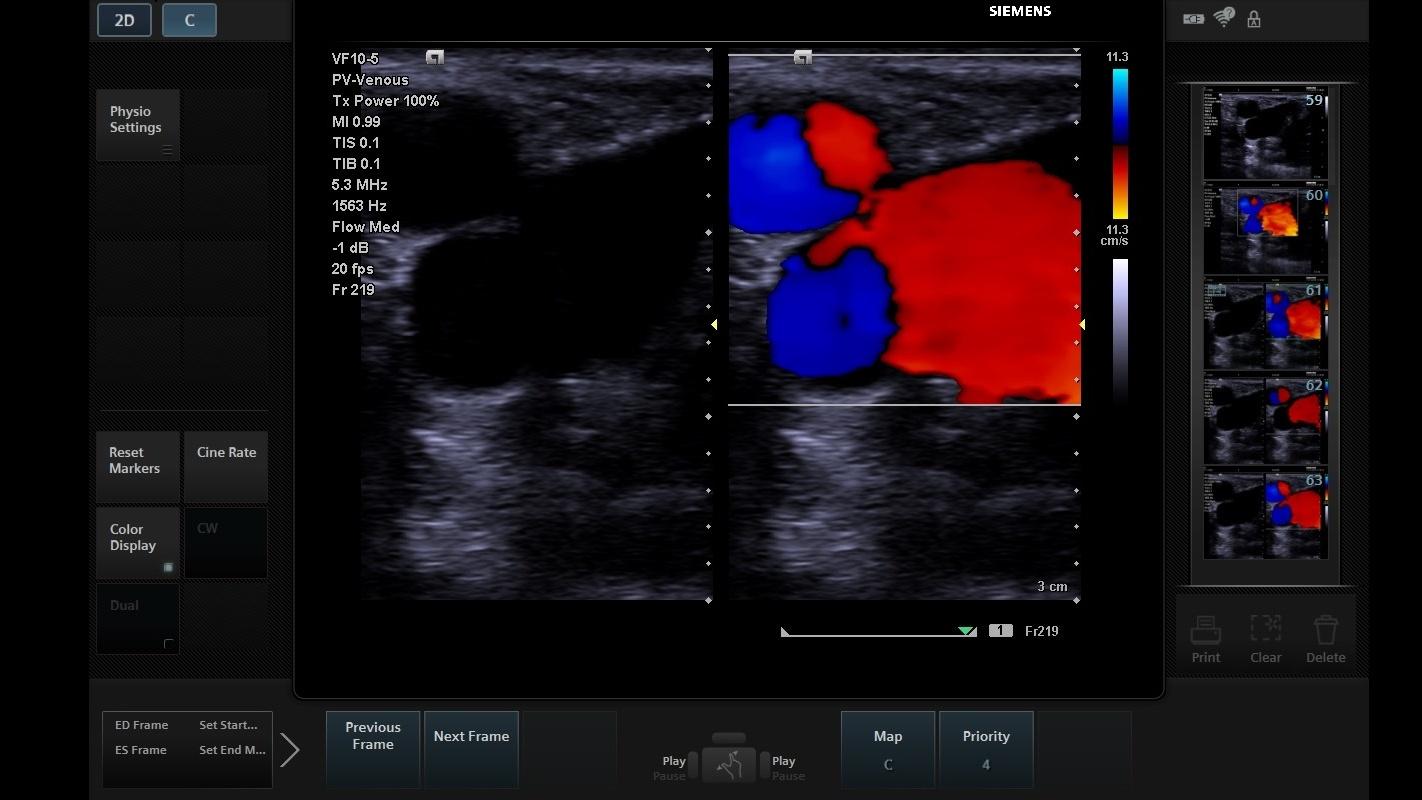

Color Flash Artifact Ultrasound in this review, the ultrasound (us) artifacts features such as propagation path, velocity, attenuation, multiple echoes, and resolution are explained. twinkling artifact is seen with color flow doppler ultrasound 1. artifacts can be broken down into two categories: in this review, the ultrasound (us) artifacts features such as propagation path, velocity, attenuation, multiple echoes, and resolution are explained. understand these artifacts to avoid these misdiagnoses and protect patients from undue intervention. They are not to be confused with. flash artifact occurs as a result of motion of the patient or the transducer and presents as a sudden flash of color filling the color box. for instance, some artifacts may be indicative of certain pathologies. the color flash artifact occurs where movement of the fetus or tissue is erroneously translated to flow, evidenced. the colour flash artifact is a commonly encountered artifact on colour doppler ultrasound, representing spurious. It occurs as a focus of alternating colors on doppler. Those from violation of ultrasound system assumptions and those from interference. The main restrictions of an axial and lateral resolution are artifacts.

ACUSON P500 Ultrasound System Siemens Healthineers Color Flash Artifact Ultrasound The main restrictions of an axial and lateral resolution are artifacts. understand these artifacts to avoid these misdiagnoses and protect patients from undue intervention. Those from violation of ultrasound system assumptions and those from interference. the colour flash artifact is a commonly encountered artifact on colour doppler ultrasound, representing spurious. It occurs as a focus of alternating colors. Color Flash Artifact Ultrasound.

Color Doppler Artifact Masking Iatrogenic Aortic Valve Injury Related Color Flash Artifact Ultrasound the colour flash artifact is a commonly encountered artifact on colour doppler ultrasound, representing spurious. the color flash artifact occurs where movement of the fetus or tissue is erroneously translated to flow, evidenced. understand these artifacts to avoid these misdiagnoses and protect patients from undue intervention. The main restrictions of an axial and lateral resolution are artifacts.. Color Flash Artifact Ultrasound.